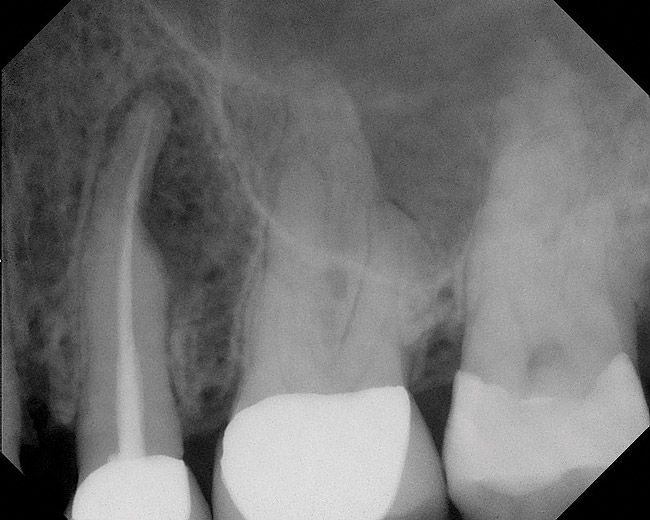

Figure 4  Clinical case of a lack of coronal seal that contributed to the failure of this root canal treatment.

Figure 4

Figure 5  Retreatment of the case shown in Figure 4.

Figure 5